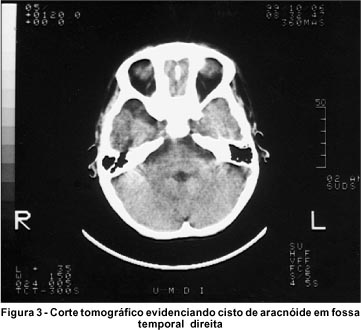

A criança apresentava desenvolvimento neuropsicomotor próprio para a idade, sem outras alterações sistêmicas. A tomografia computadorizada de crânio evidenciou um cisto de aracnóide na fossa temporal direita (Figura 3).